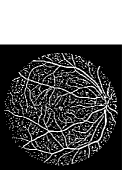

Refer to caption Refer to caption Refer to caption Refer to caption

(a)                                                                          (b)

(c)                                                                          (d)

Figure 9: Ground truth (left) and segmentation result (right): (a) and (b) are the images from DRIVE dataset, (c) and (d) are the images from the STARE dataset

V-B Vessel Segmentation Performance

The segmentation performance of the proposed model on three public available datasets is given in Table IV. It can be observed that the proposed model can achieve more than 95%percent9595\% segmentation accuracy on the DRIVE, STARE and CHASE_DB1 datasets, with the highest accuracy score Acc=96.0%𝐴𝑐𝑐percent96.0Acc=96.0\% achieved in the DRIVE dataset. Some exemplary segmentation results are shown in Fig.9. When treating the unknown regions as background regions, AUC=0.833 of trimap is 2.6%percent2.62.6\% lower than the proposed model while Acc of trimap is similar to the proposed model. In addition, Se=0.679𝑆𝑒0.679Se=0.679 of trimap is 5.7%percent5.75.7\% lower than the proposed model. These observations show that trimap can already have good segmentation performance, which indicates that the selection of region features is very effective in segmenting blood vessels. From Table IV, it can be observed that the model with vessel skeleton extraction can achieve more than 5%percent55\% increase of Sensitivity𝑆𝑒𝑛𝑠𝑖𝑡𝑖𝑣𝑖𝑡𝑦Sensitivity and 2%percent22\% increase of AUC𝐴𝑈𝐶AUC compared with the model without vessel skeleton extraction while Acc𝐴𝑐𝑐Acc of the model with vessel skeleton extraction is similar to the model without vessel skeleton extraction, which demonstrates the effectiveness of vessel skeleton extraction.